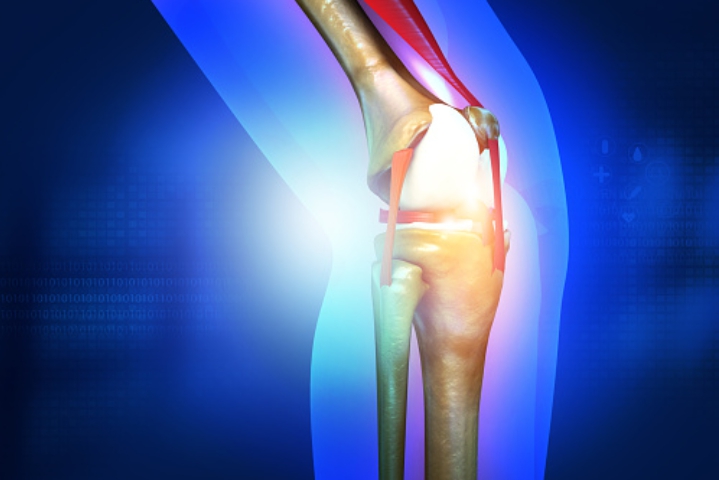

2. 콘드로이친 효능 연골 재생

콘드로이친은 연골 손상을 막을 뿐만 아니라 손상된 연골의 주요 성분인 연골세포를 재생시켜 연골 기능을 향상해 주는 역할을 합니다. 연골 손상으로 고통을 호소하는 사람들에게 도움이 됩니다.